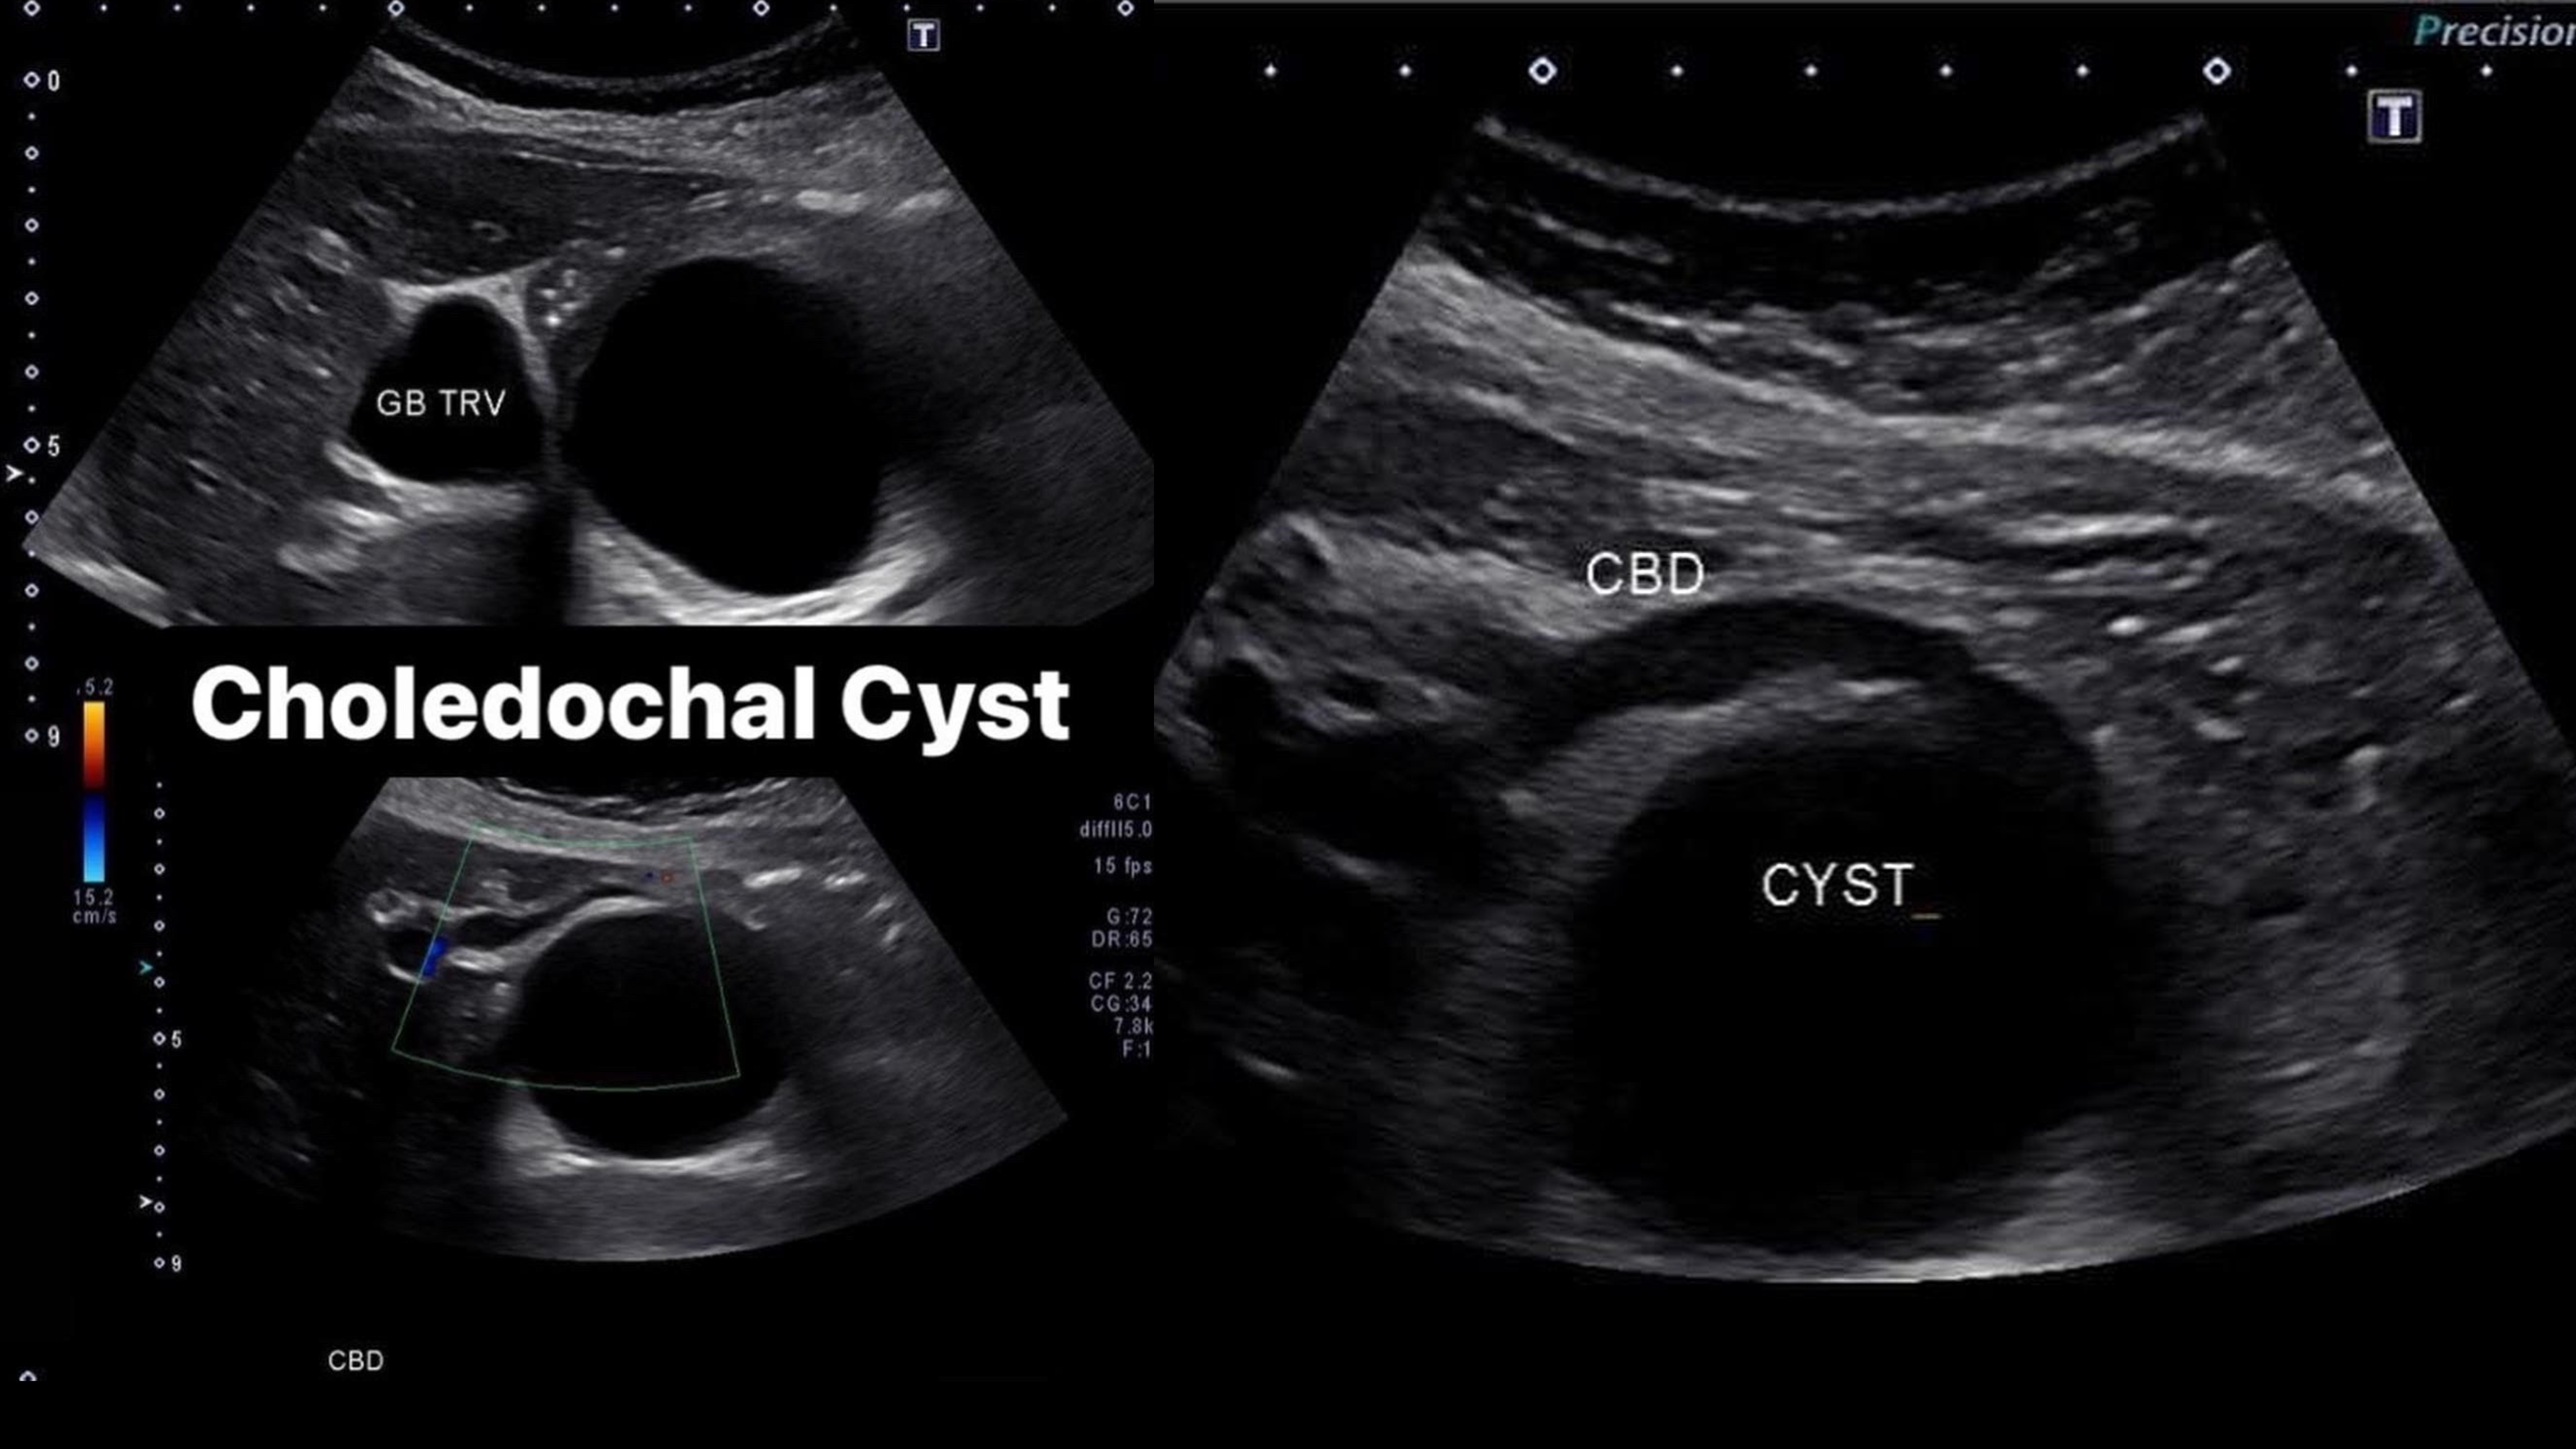

From sonographictendencies.com

Choledochal Cyst Sonographic Tendencies Type Ic Choledochal Cyst Choledochal cyst is a congenital cystic dilation of a part of bile duct that occurs most commonly in the main part of common. Characterized by fusiform dilation of the extrahepatic bile duct. Type i cysts are a dilatation of the extrahepatic bile duct. Biliary cysts, also termed choledochal malformations, are cystic dilations that may occur singly or in multiples throughout.. Type Ic Choledochal Cyst.

Choledochal Cyst Sonographic Tendencies Type Ic Choledochal Cyst Biliary cysts, also termed choledochal malformations, are cystic dilations that may occur singly or in multiples throughout. Characterized by fusiform dilation of the extrahepatic bile duct. Choledochal cyst is a congenital cystic dilation of a part of bile duct that occurs most commonly in the main part of common. A choledochal cyst (cc) or biliary cyst is a congenital or. Type Ic Choledochal Cyst.

Choledochal Cyst Sonographic Tendencies Type Ic Choledochal Cyst A choledochal cyst (cc) or biliary cyst is a congenital or acquired anomaly affecting the biliary tree. Type i cysts are a dilatation of the extrahepatic bile duct. Biliary cysts, also termed choledochal malformations, are cystic dilations that may occur singly or in multiples throughout. Characterized by fusiform dilation of the extrahepatic bile duct. Choledochal cyst is a congenital cystic. Type Ic Choledochal Cyst.